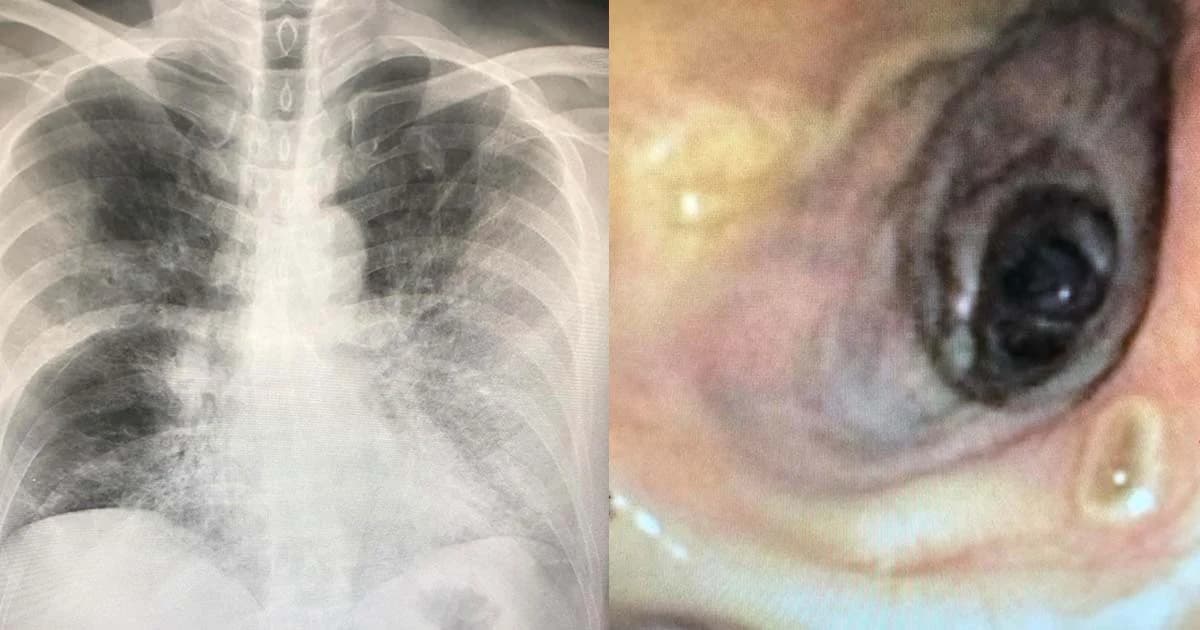

ผู้ป่วยชายไทยอายุ 57 ปี ปกติแข็งแรงดี ไม่มีโรคประจำตัว สูบบุหรี่ครึ่งซองต่อวัน ก่อนหน้าไม่สบายไปเยี่ยมเพื่อนที่ป่วยในโรงพยาบาลติดต่อกันหลายวัน เริ่มไอแห้งๆ มีไข้ และเหนื่อยมาก 3 วัน ไม่ปวดหัว ไม่ปวดตัว ไม่มีน้ำมูก ไม่เจ็บคอ เข้านอนรักษาในรพ. เอกซเรย์ปอดผิดปกติมีฝ้าขาวทั้งสองข้าง (ดูรูป) คลื่นหัวใจปกติ ตรวจหัวใจด้วยคลื่นความถี่สูง( Echocardiogram ) พบการบีบตัวของหัวใจห้องซ้ายล่าง ( Ejection Fraction ) ปกติ ระดับออกซิเจนในเลือดต่ำมาก ตรวจหาเชื้อไข้หวัดใหญ่จากช่องจมูกด้วยวิธีที่รวดเร็วให้ผลลบ แต่ก็ให้ยารักษาไข้หวัดใหญ่ Tamiflu จนครบ 5 วัน ให้ยาปฏิชีวนะ และสเตียรอยด์ ผู้ป่วยยังเหนื่อย ต้องให้ออกซิเจนตลอดเวลา เอกซเรย์ปอดไม่ดีขึ้น ทำคอมพิวเตอร์ปอดเห็นผิดปกติข้างซ้ายมากกว่าข้างขวา(ดูรูป) ต่อมาปอดข้างขวารั่วประมาณ 15 % ช่วงสัปดาห์ที่ 2 อาการดีขึ้นเล็กน้อย ปอดรั่วดีขึ้น ต่อมาแย่ลงอีก

วันที่ 17 ที่นอนในรพ.เหนื่อยมาก เอกซเรย์ปอดแย่ลง (ดูรูป) ต้องใส่เครื่องช่วยหายใจ ถึงแม้จะให้ออกซิเจน 100% ระดับออกซิเจนในเลือดก็ยังต่ำมาก ส่องกล่องเข้าไปดูในหลอดลม เห็นตุ่มเล็กๆในหลอดลมใหญ่ด้านขวา(ดูรูป)หลายตุ่ม ดูดเสมหะในหลอดลมและตัดชิ้นเนื้อส่งตรวจพบเชื้อราสายเป็นจำนวนมาก(ดูรูป) ส่งตรวจหาสารพันธุกรรม PCR ของไข้หวัดใหญ่จากเสมหะในหลอดลมพบไข้หวัดใหญ่สายพันธุ์ A ได้ให้ยารักษาไข้หวัดใหญ่ตัวใหม่ Xofluza และยาฆ่าเชื้อราวอริโคนาโซล (voriconazole) ร่วมกับยาฆ่าเชื้อรา Ambisome ผลเพาะเชื้อราขึ้นเชื้อ Aspergillus fumigatus และ Aspergillus flavus (ดูรูป) ได้ให้ยาฉีดเพิ่มภูมิคุ้มกันอิมมูโนโกลบูลินจี (IgG) ผู้ป่วยก็ไม่ดีขึ้น ในที่สุดเสียชีวิตหลังจากนอนรักษาในโรงพยาบาลเกือบ 30 วัน